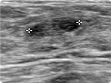

| 16 | 복부 초음파 검사 | 검진동 4층 | 약 15분 | 간, 담도, 신장, 췌장, 비장 등의 질환 |   |

| 17 | 갑상선 초음파 검사 | 검진동 4층 | 약 15분 | 갑상선비대증, 갑상선암 및 기타 이상질환 |    |